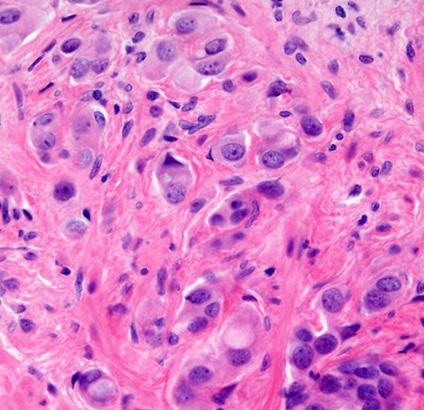

Anew UCLA study has found that artificial intelligence could help doctors identify prostate cancer patients most likely to benefit from targeted treatment that removes cancer while sparing healthy tissue, according to a UCLA-led study published Tuesday.

Researchers evaluated the new Unfold AI software that uses data from MRIs and biopsies to generate a detailed 3D map of prostate tumors. The study found that the AI technology's measurements of tumor size — compared with relying solely on tumor grade or prostate-specific antigen levels — significantly improved doctors' predictions of successful treatment.

"By using AI to measure the size of a man's prostate tumor more precisely, we can better predict who is likely to be cured with focal therapies like partial gland cryoablation," Dr. Wayne Brisbane, assistant professor of urology at UCLA's David Geffen School of Medicine,

said in a statement.

The study tested whether Unfold AI's tumorvolume mapping would aid doctors in predicting a patient's likelihood for successful outcomes from a treatment called "partial gland cryoablation," a minimally invasive procedure that freezes and eradicates only cancerous areas of the prostate instead of removing or irradiating the entire gland. The treatment minimizes damage to vital areas, which reduces side effects in an effort to maintain patients' quality of life, researchers found. Current methods of predicting treatment success — tumor grade and PSA levels — often underestimate tumor size can miss smaller cancerous areas, often leading to incomplete treatment and cancer recurrence.

"The study marks an important advance in integrating AI into prostate cancer treatment decisionmaking, offering the potential for more personalized prostate cancer care,"

TBrisbane said.

Although the findings are promising, researchers emphasized the need for broader trials to validate the results.

“Such a method has not been previously available," Dr. Leonard Marks, professor and deKernion Endowed Chair in Urology UCLA's medical school, said in a statement. "It's important because tumor volume is a major determinant of treatment success or failure."

Marks, who is also a member of the UCLA Health Jonsson Comprehensive Cancer Center and senior author of the study, added, "Using AI to predict tumor volume and shape gives a clearer picture and could help choose better candidates for focal cryotherapy.”

Unfold AI was developed by researchers at UCLA and Avenda Health.

The study was published in BJUI Compass, a peerreviewed medical journal specializing in urology, and is available online at pmc. ncbi.nlm.nih.gov/articles/ PMC11771490.